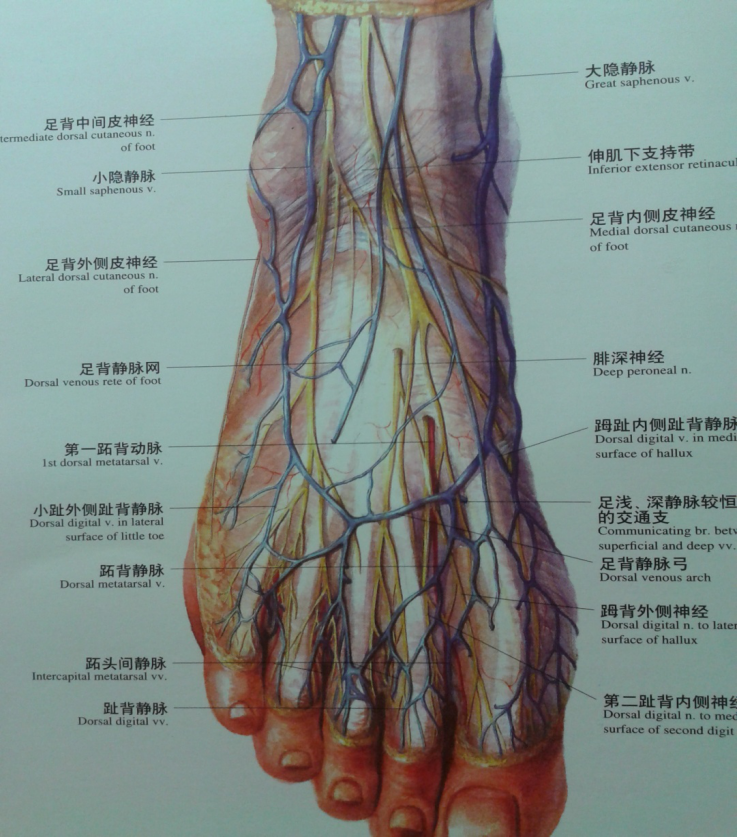

踝关节不稳定4踝伸肌下支持带解剖

图片尺寸826x1216